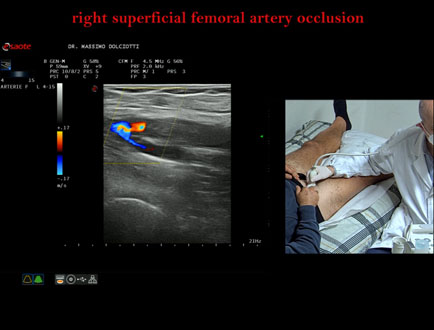

Data inserimento: 22/10/2025

Ecografia del: 13/10/2025

Strumento: Esaote MyLab Eight

Sonda: Lineare Multifrequenza 4-15 MHz

Età Paziente: M 42 anni

Motivazione dell'esame: da 2-3 mesi dolore al polpaccio destro.

Commento all'esame: le immagini ed il video documentano l'ostruzione completa dell'arteria femorale superficiale destra all'origine.

Conclusioni: occlusione dell'arteria femorale superficiale destra all'origine (occlusion of the right superficial femoral artery at the origin).

Presentazione: Dr. Massimo Dolciotti - Ancona